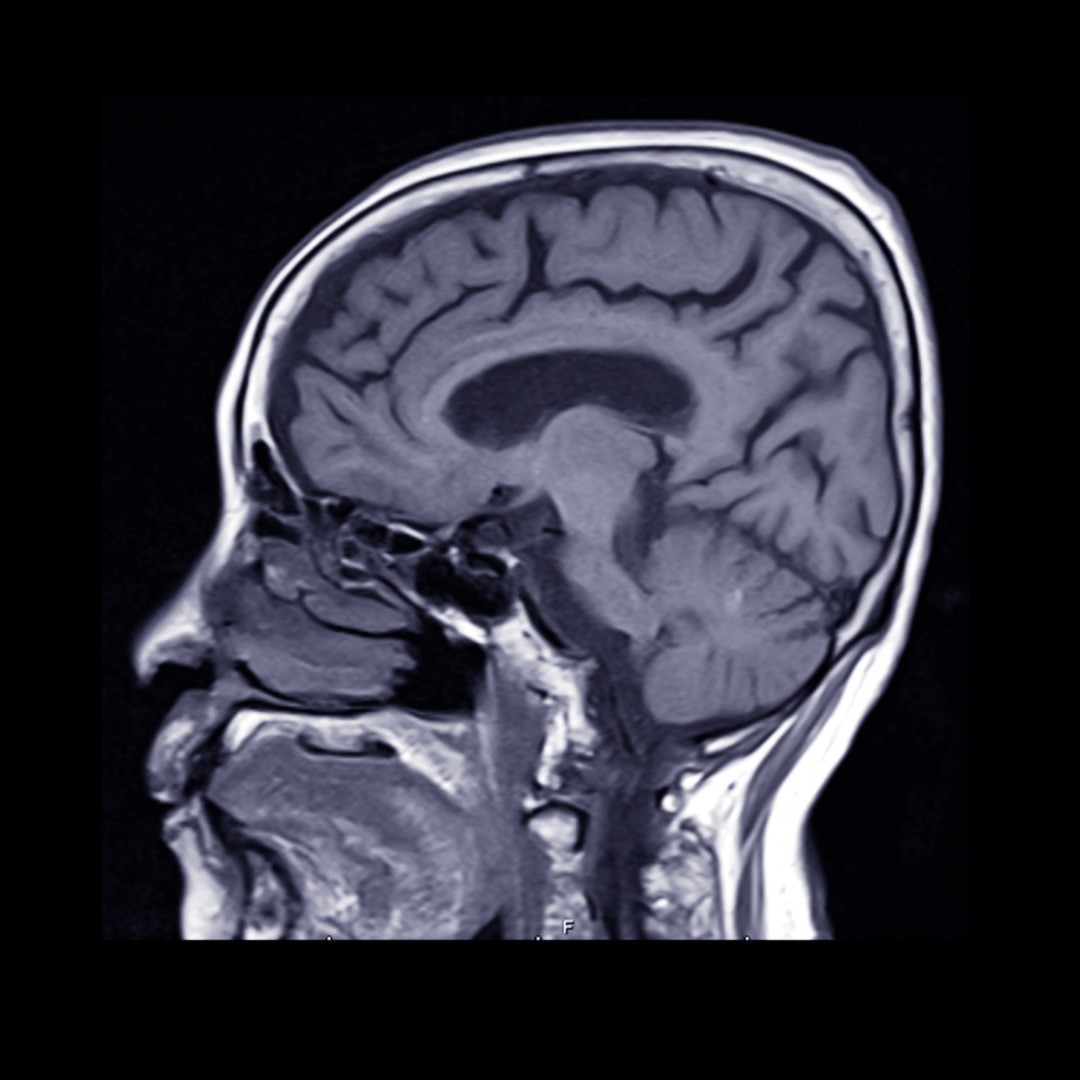

Surgical Clipping – During this surgical procedure, a tiny clip is attached to the base of the aneurysm to prevent blood flow— thereby decreasing the likelihood of it bursting or rupturing if it’s pre-rupture or to treat a ruptured aneurysm. To reach the aneurysm, the neurosurgeon performs a small craniotomy, which temporarily removes a portion of the skull, and an incision in the brain covering called the dura mater allows the surgeon to carefully retract the brain and trace the affected artery to the aneurysm. Once there, the clip is placed on the neck of the aneurysm.